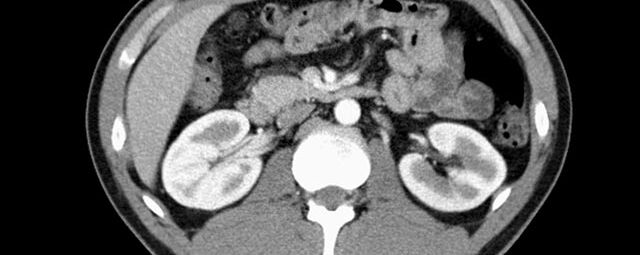

Abdomen (Bauch und Becken)

• Diagnostik von entzündlichen und tumorösen Erkrankungen der Bauchorgane

• Diagnostik von akuten Notfällen wie Darmverschluss, Hohlorganperforation oder Traumafolgen

• Darstellung der großen Gefäße zur Erkennung von Gefäßverschlüssen (z. B. Mesenterial - Arterienembolie oder Einengungen von Gefäßen (z. B. Nierenarterien)

• Darstellung und Therapieplanung von Aneurysmen (CT- Angiographie)

• Virtuelle Kolonographie zur Darstellung des Dickdarmes z. B. bei Kontraindikation zur Darm-Spiegelung oder nur unvollständig durchführbarer Koloskopie.